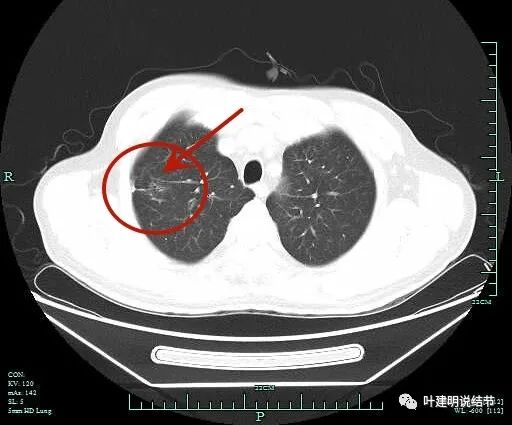

病史摘要:患者主因“检查发现肺部阴影5年”就诊。5年前当地医院体检发现肺部结节,无不适症状。1周前于杭州市肿瘤医院检查,右肺上叶后段结节倾向于MIA或AIS,余两肺微小结节建议年度复查,附见脂肪肝、左肾结石。患者起病来一般情况良好,有高血压病史10年,口服药物控制。 诊疗过程:查体未提及。影像显示2021 - 2025年结节有变化,考虑早期肺癌可能性大,鉴别诊断包括支气管腺瘤、原位癌伴肺泡